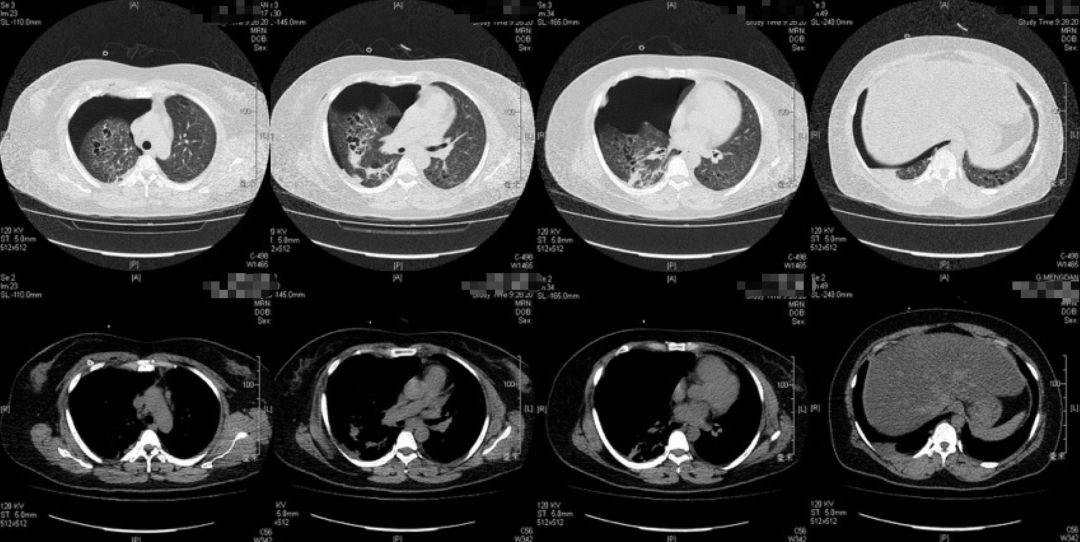

胸部影像学检查

2019-5-13我院胸片

2019-5-14我院胸部CT平扫

患者青年女性,因「咳嗽、咳痰、咯血半月余,胸痛8天」入院,急性起病,逐渐加重,胸部CT提示右侧气胸,双肺相对弥漫分布的气囊与结节,沿气管血管束分布,右下肺实变。肺部弥漫性囊泡样疾病,需要考虑肺淋巴管平滑肌瘤病(LAM)、BHD综合征、肺朗格汉斯组织细胞增生症(PLCH)、淋巴细胞性间质性肺炎(LIP)、感染性疾病如耶氏肺孢子菌肺炎(PCP)等疾病。LAM一般常见于育龄期女性,影像学以弥漫均匀分布的薄壁囊泡为主要表现,此例患者为年轻女性,肺部多发囊泡,需要考虑LAM,但囊泡不是薄壁,分布不均匀,形状不规则,不符合LAM的典型表现。PLCH一般多见于吸烟患者,影像学以奇形怪状的沿支气管血管束分布的囊泡样改变为特点,吸烟患者一般以上叶及中叶病变为主,不累及肋膈角,多系统病变患者可以累及肋膈角,本例需考虑PLCH可能。BHD综合征肺部表现为多发薄壁囊肿,形状不规则,多于基底部、外周、沿纵隔分布,其他系统表现可合并皮疹、肾肿瘤等,可有家族史,本例患者无BHD家族史,需进一步排查其他器官有无病变。LIP常有肺部多发囊泡改变,一般合并自身免疫性疾病,该患者需进一步完善自身抗体等风湿免疫相关指标,协助诊断。此外,还需考虑PCP、金葡菌感染等感染性疾病。PCP多见于免疫抑制宿主,可以有多发性肺气囊的表现,该患者无发热,无免疫抑制病史,目*考前**虑可能性不大。

本例患者的胸部CT主要表现为两肺相对弥漫分布的怪异的气囊和结节,气囊为薄壁,以中上肺分布为主,沿支气管血管束分布,符合LCH细胞沿支气管分布的特点,并且有可能会引起支气管阻塞,类似活瓣样的作用,因此囊腔的形状怪异。胸腔镜术后的CT表现,可能是局部阻塞牵拉引起疱的加重,也可能是胸膜粘连后局限性的气胸的表现。